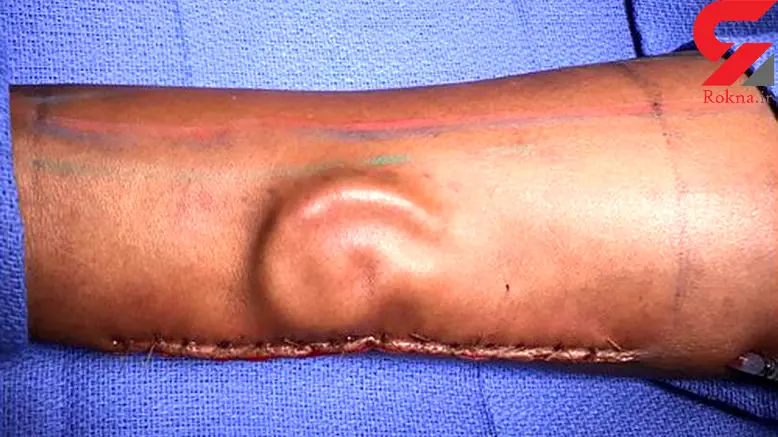

روش جدید پیوند گوش در آمریکا شنوایی یک سرباز را به او برگرداند.